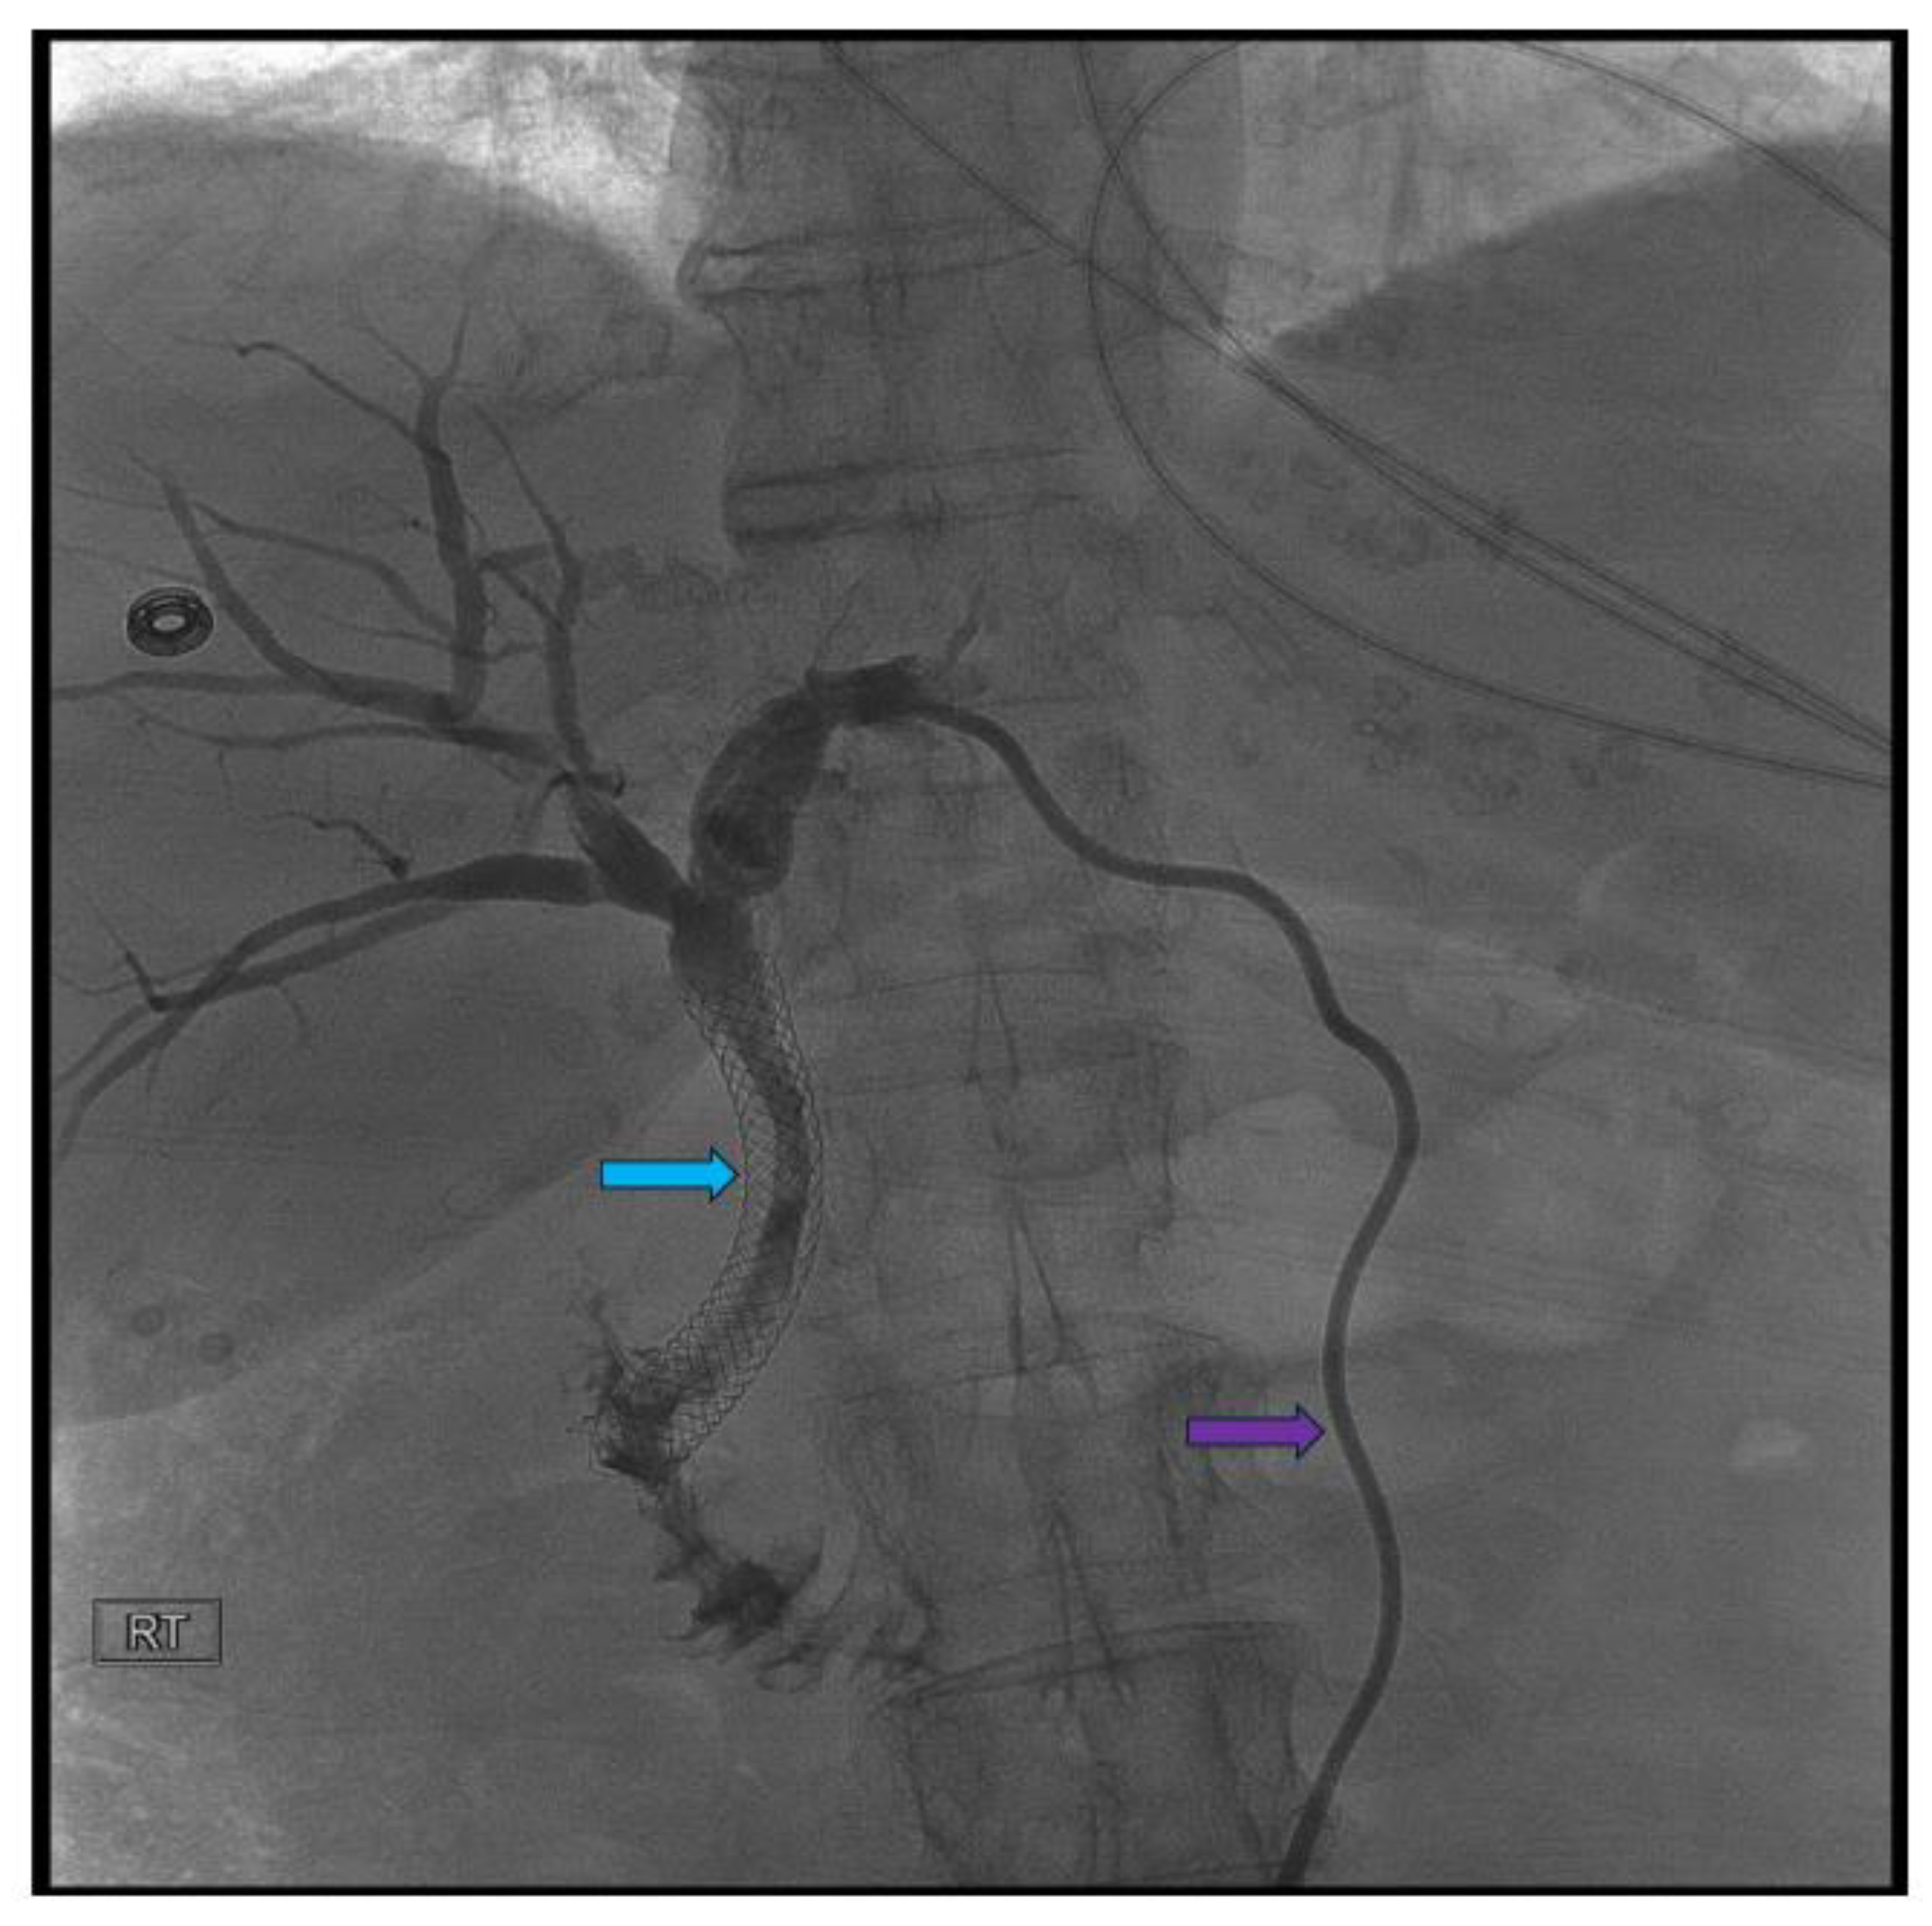

Pancreatic cancer is an aggressive malignancy, and the current 5-year survival rate in the United States, according to the Surveillance, Epidemiology, and End Results Program data, approximates 12%. Although the current standard for resectable pancreatic cancer most commonly includes neoadjuvant chemotherapy prior to a curative resection, surgery in the majority of patients has historically been palliative. The latter interventions include open or laparoscopic bypass of the bile duct or stomach in cases of obstructive jaundice or gastric outlet obstruction, respectively. Non-surgical interventional therapies started with percutaneous transhepatic biliary drainage (PTBD), both as a palliative maneuver in unresectable patients with obstructive jaundice and to improve liver functions in patients in whom surgery was delayed. Likewise, interventional radiologic techniques included placement of plastic and ultimately self-expandable metal stents (SEMS) through PTBD tracts in patients unresectable for cure as well as percutaneous cholecystostomy in patients who developed cholecystitis in the context of malignant obstructive jaundice. Endoscopic retrograde cholangiopancreatography (ERCP) and stent placement (plastic/SEMS) was subsequently used both preoperatively and palliatively, and this was followed by, or undertaken in conjunction with, endoscopic gastro-duodenal SEMS placement for gastric outlet obstruction. Although endoscopic ultrasound (EUS) was initially used to cytologically diagnose and stage pancreatic cancer, early palliation included celiac block or ablation for intractable pain. However, it took the development of lumen-apposing metal stents (LAMS) to facilitate a myriad of palliative procedures: Cholecystoduodenal, choledochoduodenal, gastrohepatic and gastroenteric anastomoses for cholecystitis, obstructive jaundice, and gastric outlet obstruction, respectively. In this review, we synopse these procedures which have variably supplanted surgery for the palliation of pancreatic cancer in this rapidly evolving field.

Endoscopic Retrograde Cholangiopancreatography